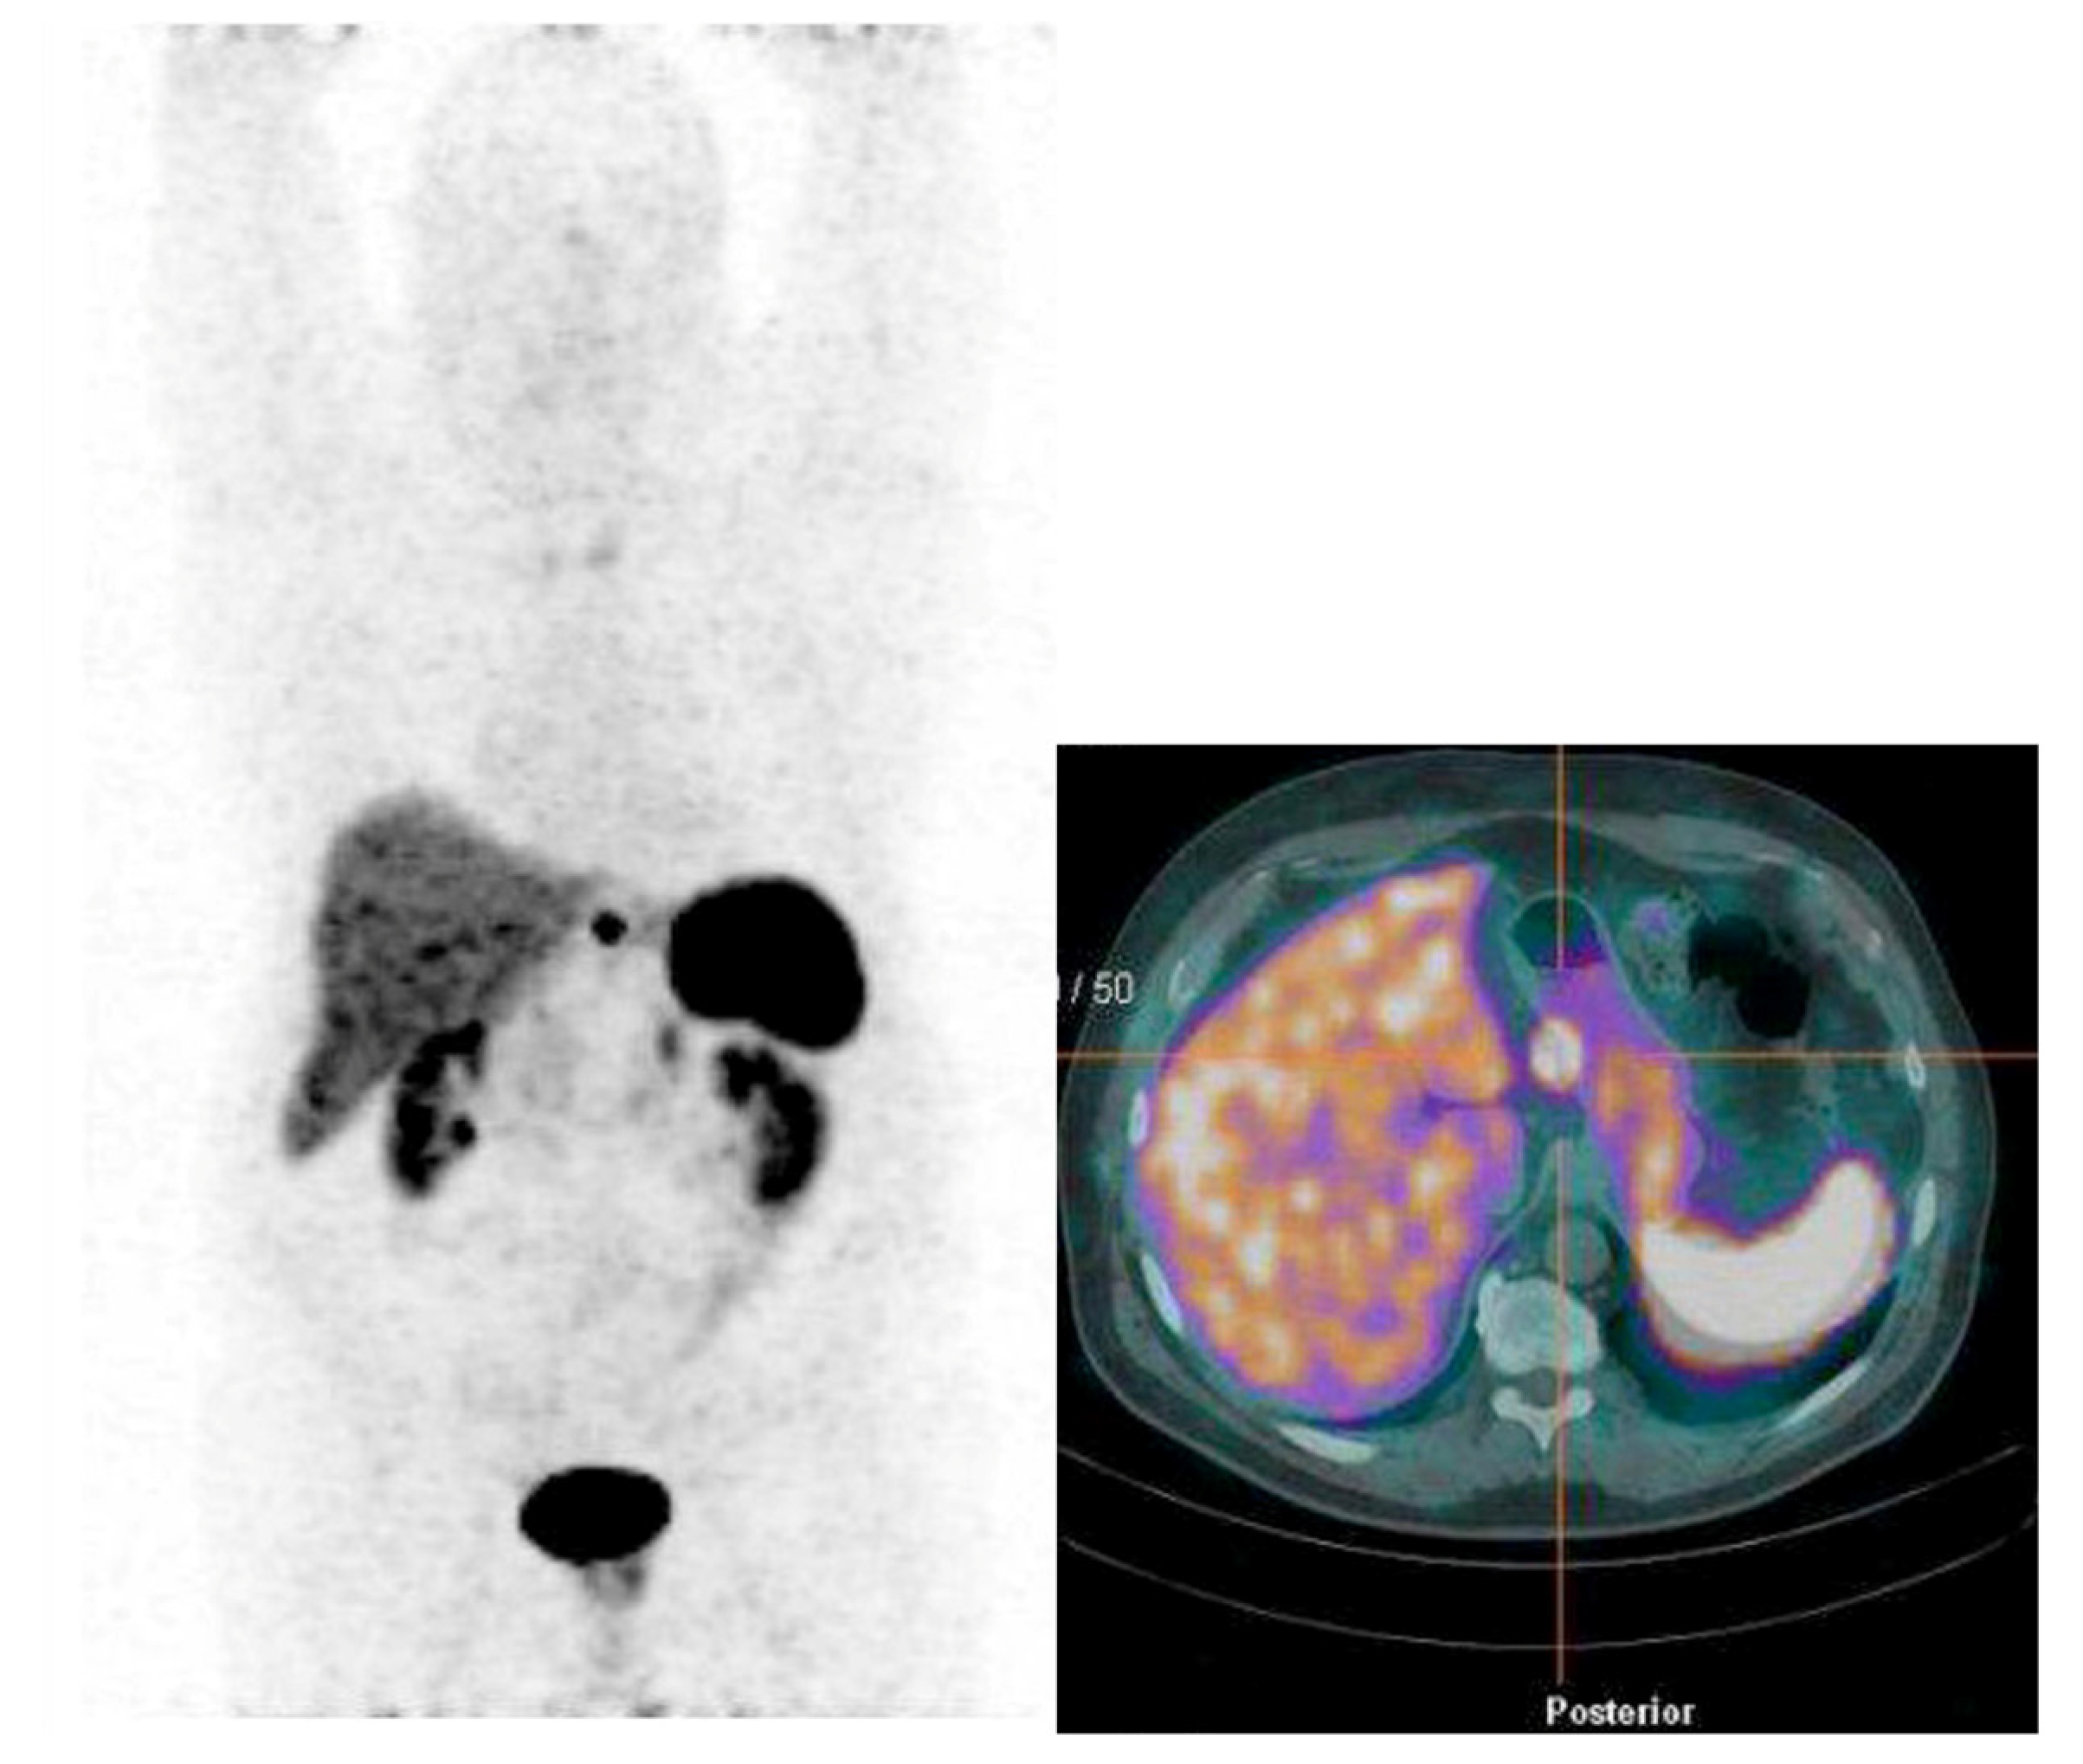

| Patient 6 | 50 mm | 4% | No | No | Yes | No | - | No | Yes |